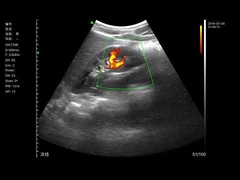

Kwaliteit Draagbare ultrasone Scanner, handbediende Ultrasone klankscanner Fabrikant uit China

Alle video's